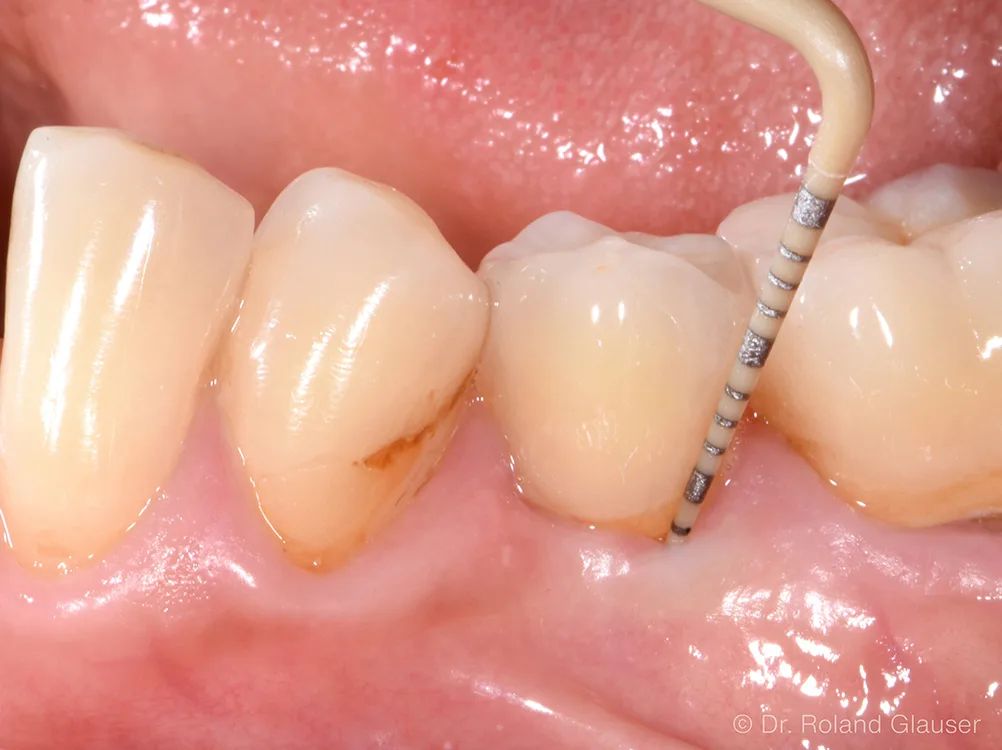

Die mukosale Schutzbarriere schirmt das Gewebe vor Plaquemigration und Krankheitserregern wie Bakterien ab (Abb. 2). Dadurch können Zahnersatzspezialisten die Gewebegesundheit bei ihren Patienten erhalten und die für Zahnimplantate typischen Nebenwirkungen (43% Mukositis und 22% Periimplantitis6) deutlich reduzieren respektive gänzlich vermeiden.1, 2 Dies ermöglicht langfristig stabile ästhetische Resultate.1

- Mukosale Schutzbarriere verhindert Plaquemigration entlang des Patent™ Halsbereichs tief in die Gewebe (Abb. 2).3-4

- Patent™ Symbionic Teeth zeigen nach 9 Jahren durchschn. Sondierungstiefe von 3 mm (entspricht dem Benchmark eines gesunden natürlichen Zahns; Abb. 3).1